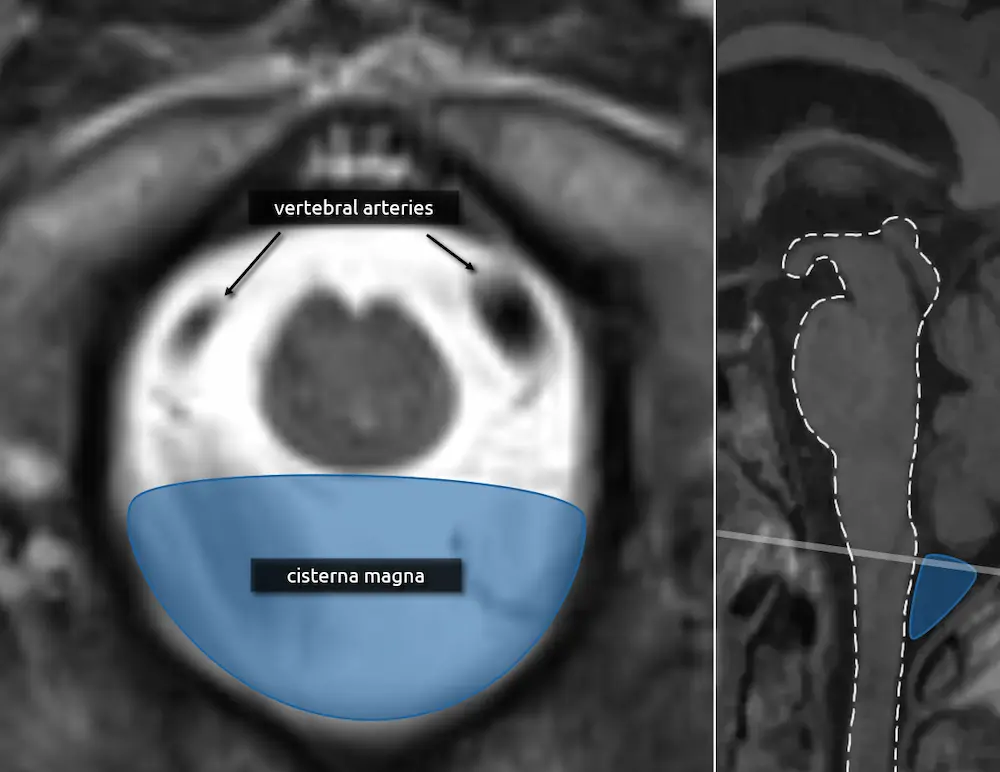

The transition of the medulla to the cervical spinal cord is approximated by the foramen magnum. At this point, the medulla is nearly completely round.

1. Vertebral arteries

2. Cisterna magna

The cisterna magna is the largest CSF space in the brain and is located posterior to the lower medulla/cervicomedullary junction. The CSF space lateral to the medulla is called the lateral cerebellomedullary cistern, and the CSF space anterior to the medulla is the premedullary cistern.